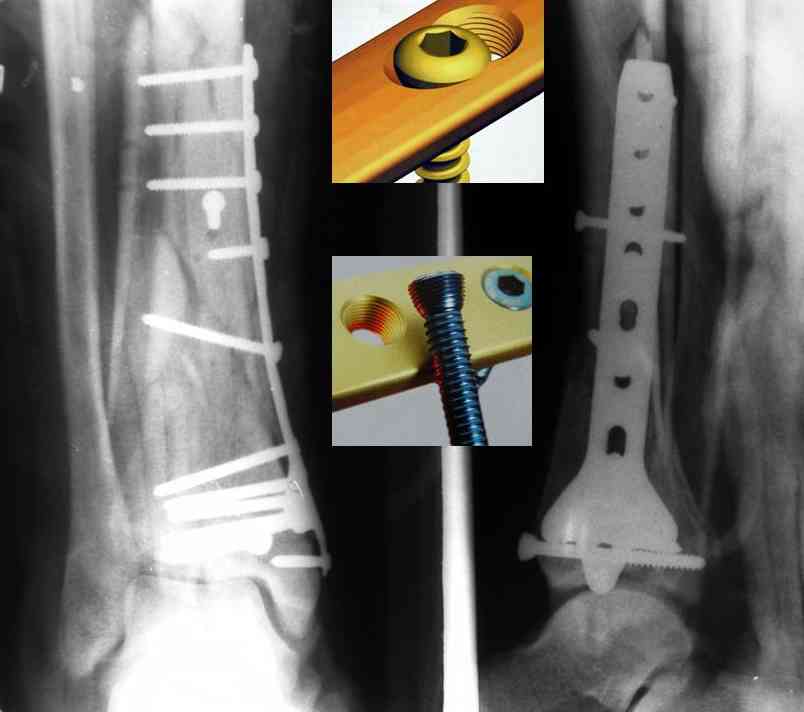

На рентгенограммах типичный перелом пилона по типу С-3. есть опыт до 100 открытых опреаций у нас в клинике. 20 примерно в год. Принцип один -все внутрисуставные переломы нуждаются в открытой репозиции и внутренней стабильной фиксации. При поступлении КТ не надо, так как получается только нагромождение костей. Истинной картины нет. Главное восстановить длину малоберцовой кости - это ключ к успеху. При поступлении меньше всего надо думать о сосудистых расстройствах, т.к. сама операция и репозиция даже сначала частичная даёт улучшение сосудитых нарушений. Причём очень быстро. Операция в 2этапа. При поступлении доступ позади наружной лодыжки, причём обязательно. После этого репозиция малоберцовой кости и фиксация пластиной 1/3 трубки под винт 3,5. Дренаж и любой аппарат наружной фиксации. Затем после спадения отёка на 5-7-10 день аппрат снимается и дугообразный разрез спереди от медиальной лодыжки 10-12 см. Главной чтобы расстояние между 1 и вторым разрезом было не меньше 7-8 см. Тогда не будет некрозов лоскутов. Таранная кость используется как матрица на неё укладываются отломки и фиксируются пицами. Ренг-контроль. Отломки лежат все отдельно, но ничего не высыпется. При переломах С-3 всегда нужна костная пластика (из крыла). Фиксация пластиной лист клевера простой или LCP. Гипс не нужен. Дренаж до 48 часов. Операция длится 3-4 часа обязательно без жгута. Посылаю примерно такой же случай.

Кстати, при переломах переднего края по классификации АО В-3 при переломах пилона пластина укладывается по передней поверхности. Она достаточно тонкая и эластичная, не надо этого бояться. Посылаю три снимка.

Ja operiroval bolnogo po Vashemu, hotia sam ni ochen' ubezden' v itom, t.k. bolnoi otkazalsa na proch' ot ex.fix, ja emu sdelal ORIF + Kostnia plastika, snimky prelogiottsa,